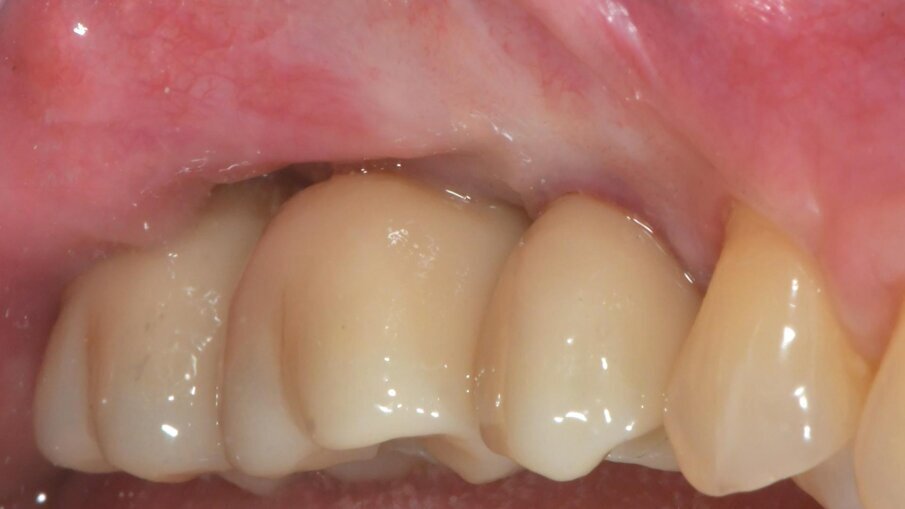

Dopo 3 mesi (T2), gli impianti sono stati esposti mediante un lembo spostato apicale per aumentare la quantità di tessuto cheratinizzato vestibolarmente agli impianti e riallineare la linea mucogengivale precedentemente spostata in direzione palatale; e sono state applicate viti di guarigione svasate per favorire una corretta guarigione trans-mucosa. Dopo 1 mese (T3), sono state eseguite corone singole in ceramica, per il primo carico funzionale e la finalizzazione provvisoria del caso, in attesa della maturazione ossea completa (Fig. 34). Dopo 6 mesi (T4), le corone sono state sostituite con corone in zirconio, per il carico funzionale e la finalizzazione definitiva degli impianti (Figg. 36-38). I controlli clinici e radiografici al primo carico funzionale, a 6 mesi, a 12 mesi, e a 24 mesi, mostrano la salute dei tessuti peri-implantari e il mantenimento dei livelli ossei peri-implantari (Fig. 39).